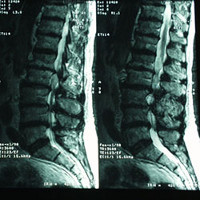

Scolioses

Généralités

Les scolioses de l'enfant (juvéniles)

Les scolioses de l'adolescent

Les scolioses de l'adulte